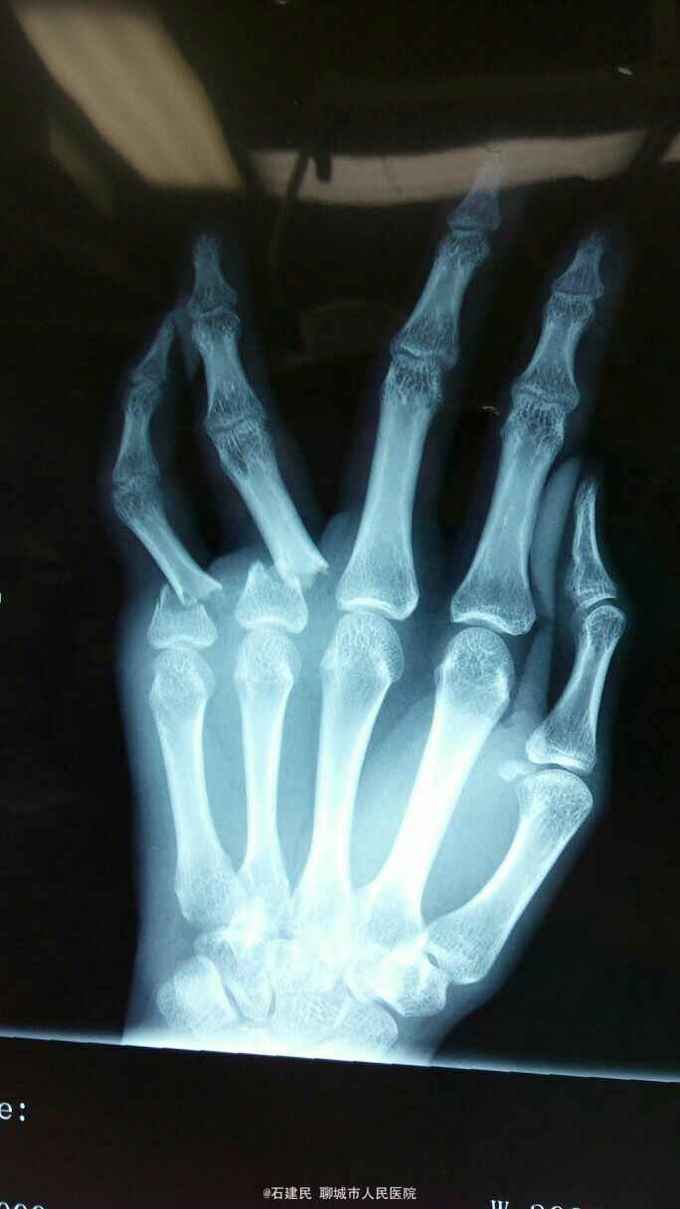

患者外伤致手部肿痛畸形,活动不能来我院就诊,行X线示环小指指骨骨折,收住院治疗。

查体可见神志清,精神正常,手背明显肿胀,畸形,环小指活动不能。

环小指指骨骨折,给予行切开复位内固定术,术中见环小指指骨近端骨折较短,给予行T型刚板固定。